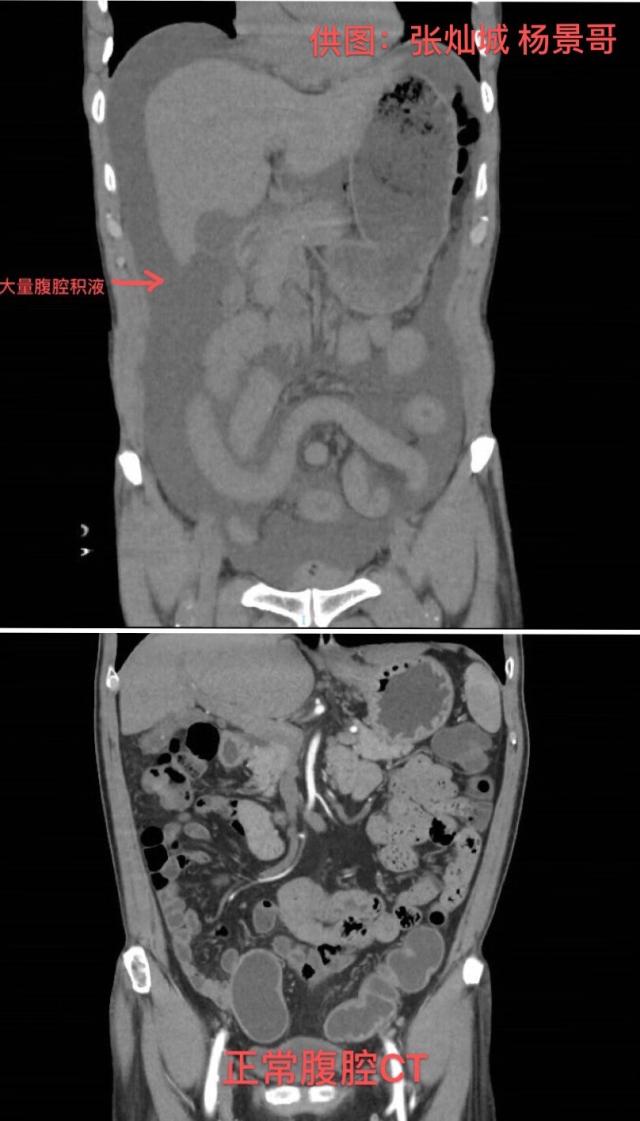

当时,陈伯腹中因大量积水而肿胀发硬,还出现了无尿症状,腹部皮肤因供血不足已出现“花斑”。结合进一步检查结果,诊断为胃穿孔弥漫性腹膜炎感染性休克。“如果不做手术,熬不过当晚。但进行手术,也有极大的风险。”汤汉林说。

暨南大学附属第一医院麻醉科主任医师李雅兰和团队维持着陈伯的生命体征,胃肠外科手术团队迅速进行手术。胃肠外科副主任医师杨景哥介绍,术中从陈伯腹部抽出了2500毫升黄绿色脓液,相当于两支可乐“大炮”,感染十分严重。胃壁上有直径1.5厘米的穿孔,胃液伴随食物残渣就是通过这个洞涌入腹腔。